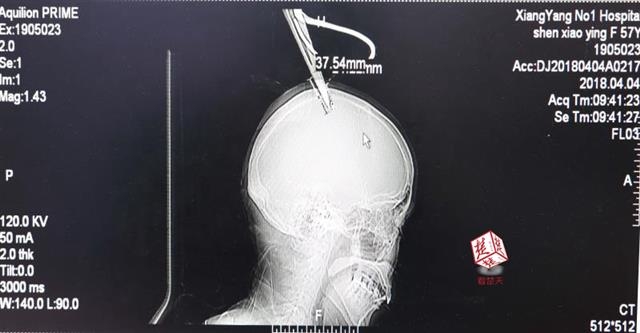

醫(yī)生檢查發(fā)現(xiàn),剪刀刀尖斜嵌在沈某顱骨里,離腦髓只有兩三毫米。所幸是斜著插進去,如果是垂直刺入,很有可能造成癱瘓。

4月4日清晨,襄陽市樊城區(qū)太平店鎮(zhèn)57歲的農(nóng)村婦女沈某,在采摘香椿嫩芽時,綁在竹桿上的剪刀因竹子腐朽不慎折斷,剪刀斜插入頭顱。經(jīng)過及時搶救,目前脫離生命危險。

醫(yī)生檢查發(fā)現(xiàn),剪刀刀尖斜嵌在沈某顱骨里,離腦髓只有兩三毫米。所幸是斜著插進去,如果是垂直刺入,很有可能造成癱瘓。最終經(jīng)過手術(shù),剪刀被取出,沈某目前仍在ICU進一步觀察。